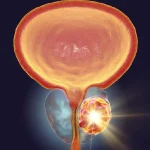

علائم سرطان پروستات میتواند بسیار نامحسوس و یا بسیار شبیه به بیماریهای ساده مردانه باشد به همین دلیل است که در ابتدای راه و زمانی که این سرطان قابل درمان است، افراد این علائم را نادیده میگیرند. برای اینکه بتوانید برای درمان سرطان پروستات به موقع اقدام کنید، باید تمامی نشانههای سرطان پروستات را در تمام مراحل آن بشناسید و به محض مشاهده آنها با متخصص مشورت کنید پس برای آشنایی بیشتر حتما این مقاله را تا انتها بخوانید.

سرطان پروستات یکی از شایعترین سرطانها در مردان است و سالانه تعداد قابل توجهی از مبتلایان تنها به دلیل عدم تشخیص زودهنگام علائم سرطان پروستات وارد مراحل پیشرفته بیماری میشوند. این بیماری در مراحل اولیه بیسر و صدا پیش میرود و بسیاری از مردان تنها زمانی متوجه نشانهها میشوند که سرطان به خارج از پروستات گسترش یافته است.

در مراحل اولیه، تومور هنوز کوچک است و فشار زیادی به مجاری ادراری وارد نمیکند به همین دلیل علائم خفیف و تدریجی ظاهر میشوند که از مهمترین آنها به شرح زیر است: